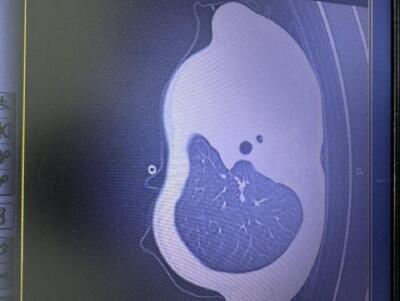

急診檢查結果顯示:小宇體內炎癥指標大幅上升,胸片更發現左側肺葉幾乎“罷工”,影像學中出現大片白色,即通常所說的“白肺”,意味著肺功能嚴重受損,孩子已經缺氧,隨時有窒息危險。

影像顯示肺白了一半。圖源:浙大兒院